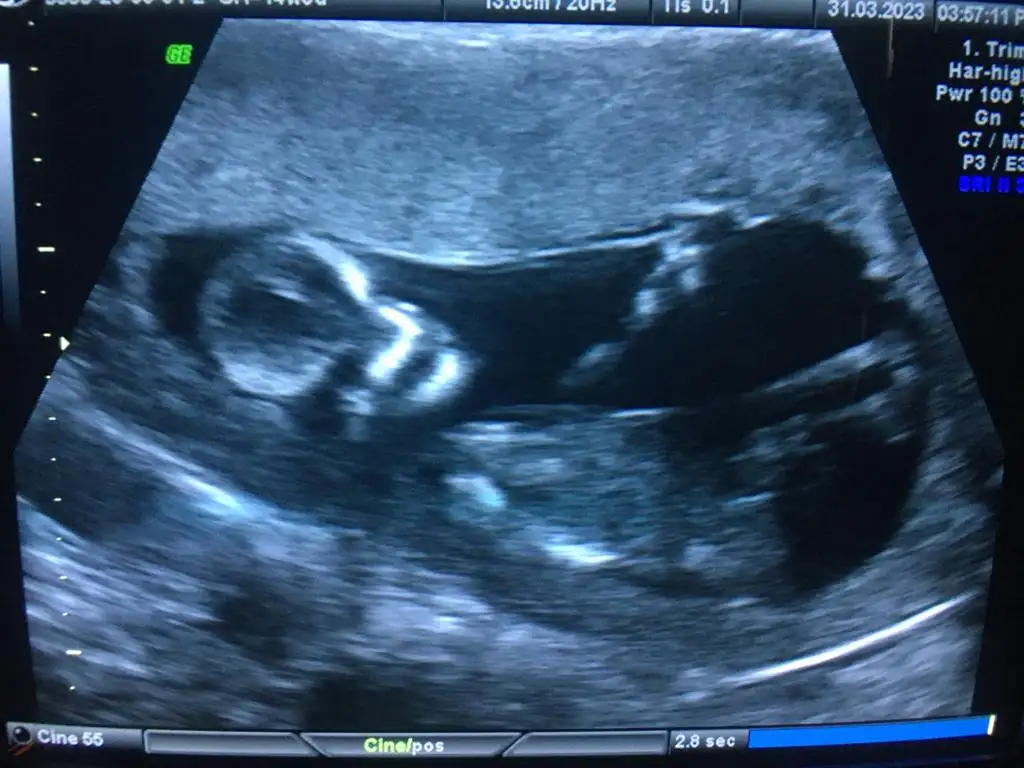

Sırayla 8-12-14 hafta hepsi karından yorumlarsanız sevinirim

12 haftalıkken erkege benziyor denildi 14 hafta kıza benziyor denildi 15 haftalık oldum hala bilmiyorum bebisimin cinsiyetini dahada doktora gitmeme 3 hafta var meraktan çatlamak üzereyim 😅